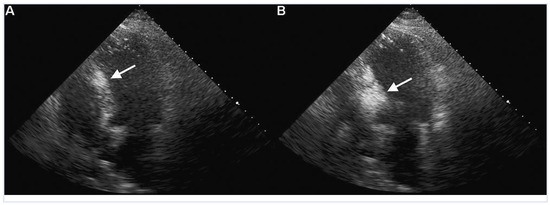

Aneurysm of the Left Circumflex Coronary Artery

by Christian Arranto, Christoph Auf der Maur and Paul Erne

Cardiovasc. Med. 2010, 13(7), 247; https://doi.org/10.4414/cvm.2010.01511 - 11 Aug 2010

Viewed by 66

Abstract

A 54-year-old man was hospitalised because of an inferior ST-elevation myocardial infarction [..] Full article

Show Figures

Figure 1